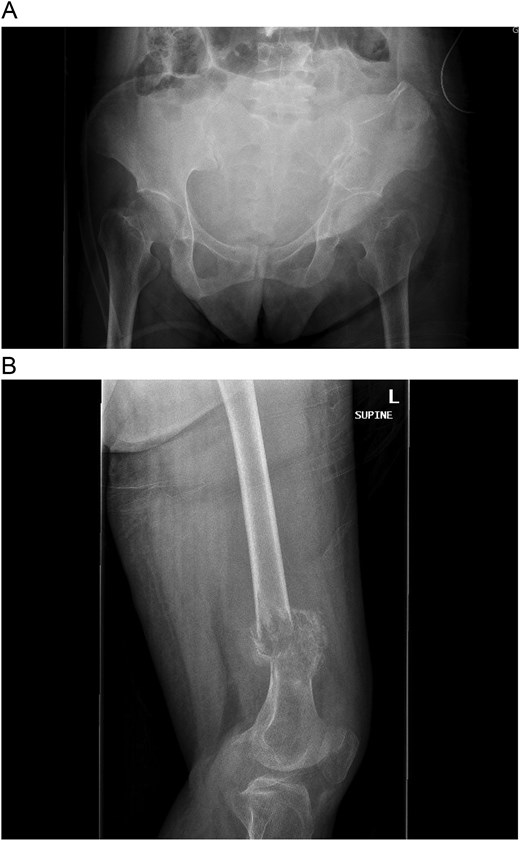

A multidisciplinary discussion involving orthopedic, maternal-fetal medicine, and head and neck teams determined the treatment plan. Further biopsy confirmed the brown tumor diagnosis, showing multinucleated giant cells, mononuclear stromal cells, bone resorption, and osteoclast clustering (Fig. 2A–C). Six days after the presentation, she was deemed suitable for parathyroidectomy. Although at high risk for pathologic fracture, she declined prophylactic fixation during pregnancy. Two days after a successful parathyroidectomy, she underwent an uncomplicated Cesarean section. As her calcium levels normalized, plans for femoral fixation were made post-childbirth. One week postpartum, the patient fell, resulting in a pathologic fracture of the left distal femur and ipsilateral iliac wing fracture (Fig. 3A and B).

(A and B) Pathologic fracture involving the left distal femur and left iliac bone.